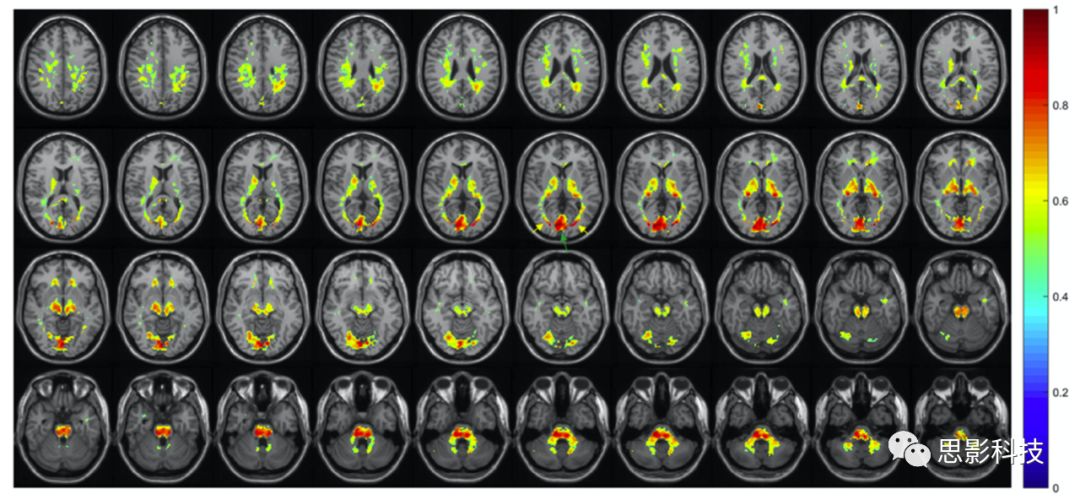

Ding等人在2013年提出了一些具有挑戰(zhàn)性觀點,他們的研究領域是關于GMWM在靜息態(tài)下的低頻振幅和其他特征。圖4的結果顯示的是來自2個被試中以WM為種子點呈現(xiàn)出時間序列相關性的腦圖。結果顯示,與其他的大部分WMGM體素相比而言,當以左側視放射為種子點時,雙側大腦半球的視放射區(qū)域呈現(xiàn)出更高的時間序列相關性。同時,當以右側胼胝體為種子點時,同樣也與其他絕大部分白質相比,雙側的胼胝體區(qū)域呈現(xiàn)出更高度的時間序列相關性。這些高相關性的腦區(qū)似乎可以延伸到很長的距離,但都僅限于特定的結構,這意味著只有這些相同的結構中存在同步的時間變化MarussichPeer等人也報道了類似的發(fā)現(xiàn),他們分別使用獨立成分分析(ICA)K-means聚類的方法對WM的同質性成分進行分離。而這些成分顯示出了相似的白質纖維的空間分布。這樣的結果表明WM纖維束提供了結構的連通性,因此在靜息態(tài)下也可能會呈現(xiàn)出同步的BOLD活動。利用這些發(fā)現(xiàn),Jiang等觀察到了在精分病人中,特定的白質成分中存在低頻自發(fā)振蕩振幅的減低。

Fig 4 左圖以左側視放射為種子點,右圖以胼胝體為種子點(2名健康被試)。